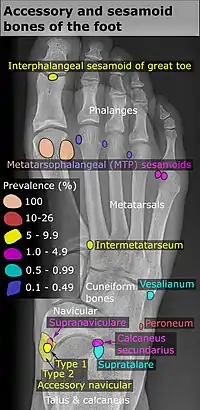

Lateral view.[11]

- 1 2 Reference list for image is located at Commons:Template:Accessory and sesamoid bones of the foot - references.